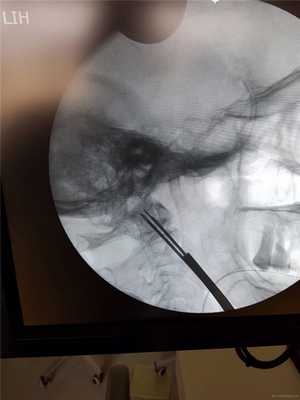

Затем под рентгеновским контролем устанавливается спица в необходимой точке ввода под нужную траекторию.

Контроль в прямой проекции.